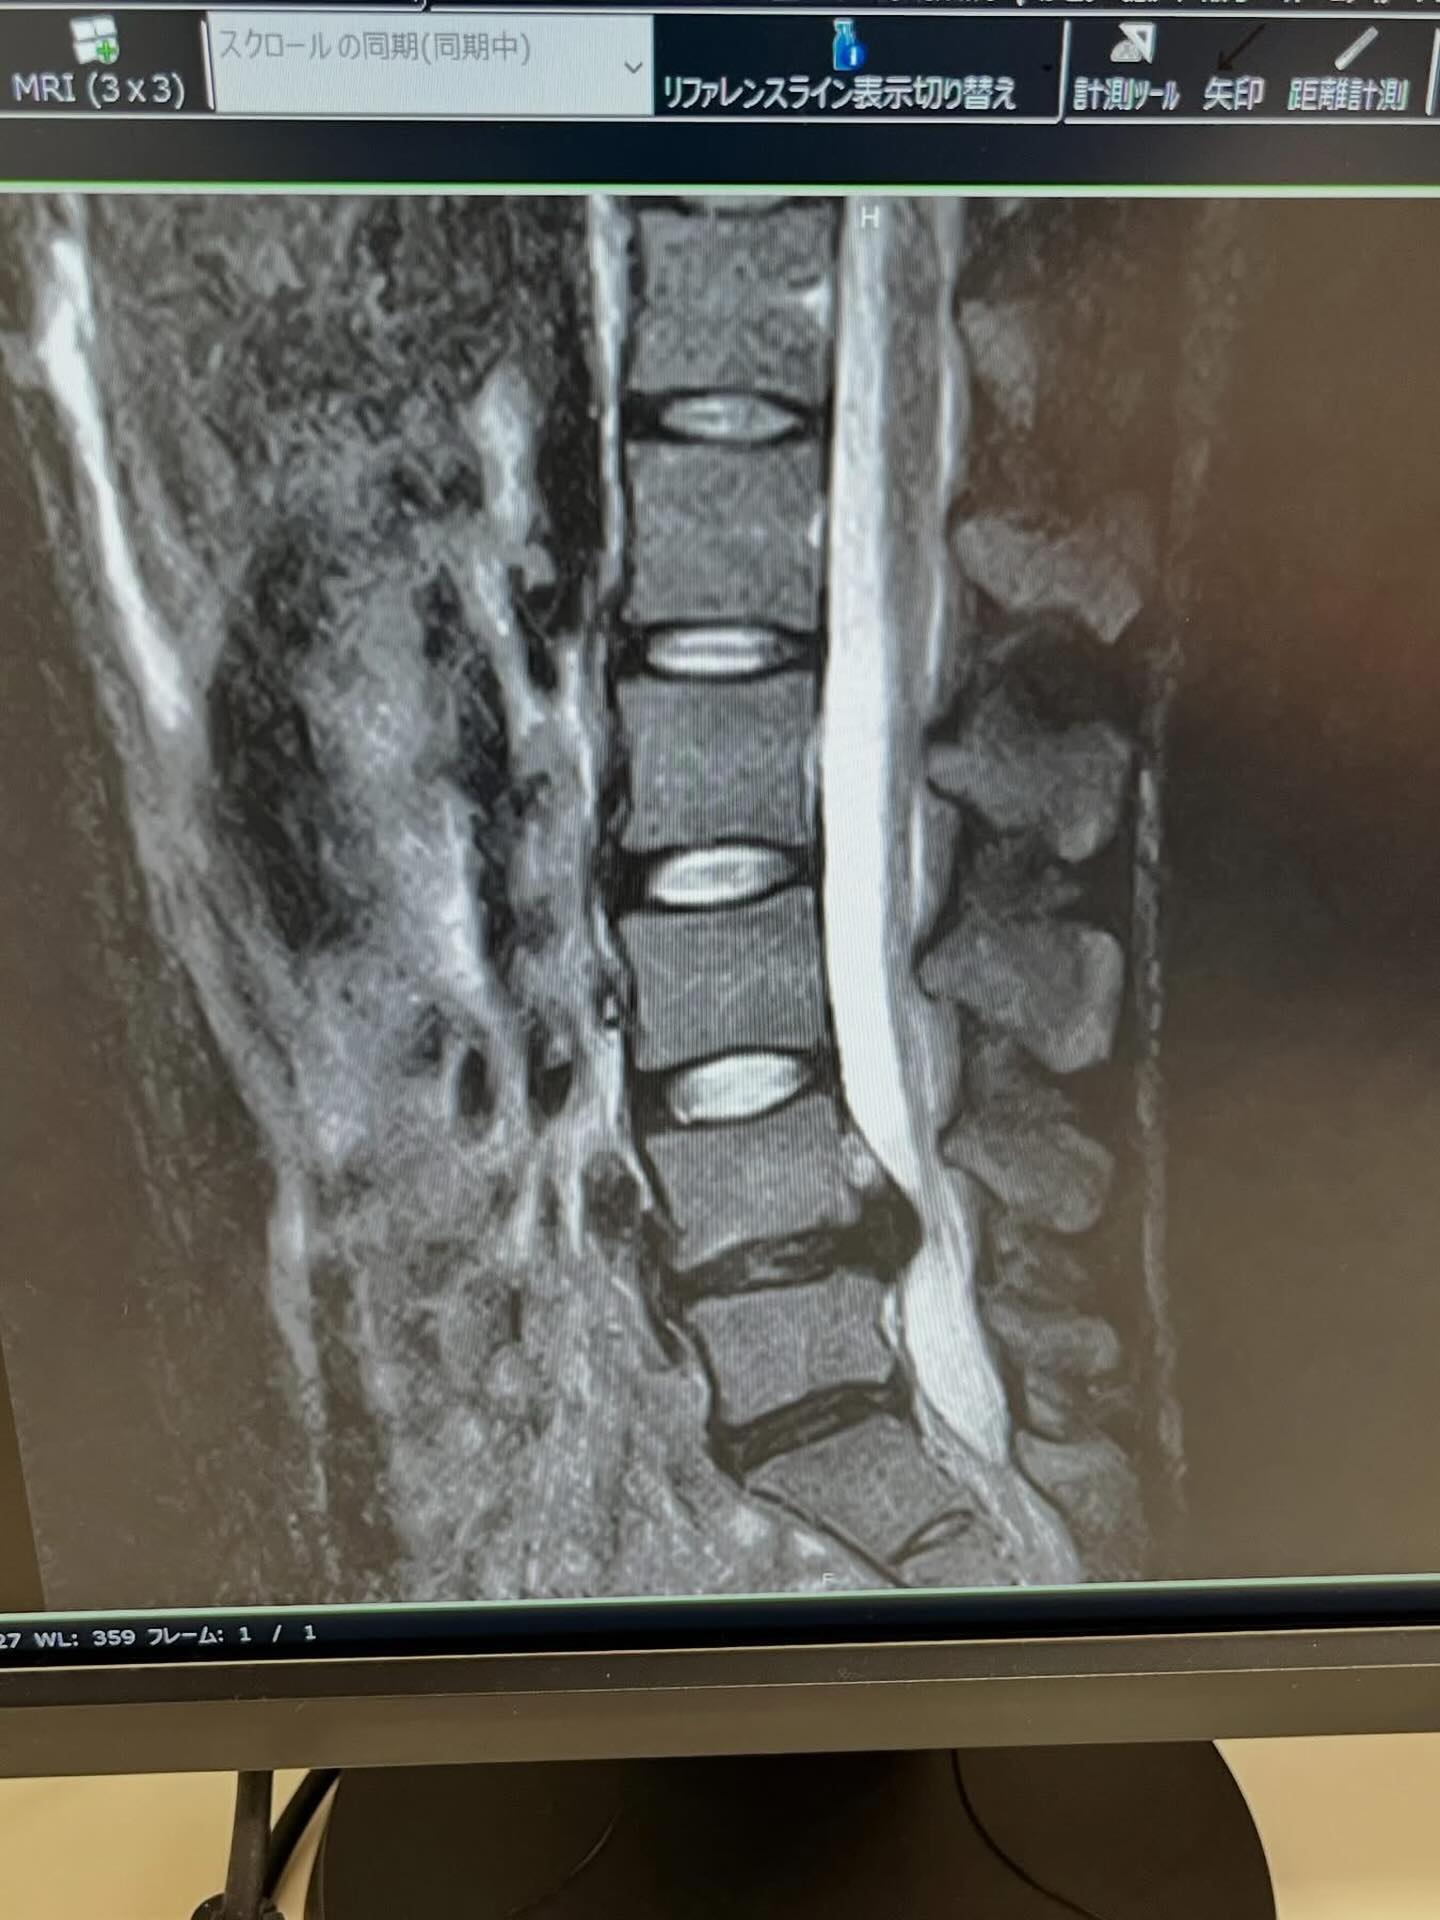

島根県で自給自足生活をしている河野 成祥(なる)が

ヘルニアになって24時間激痛が走り

杖ないとまっすぐ立てないとのこと😭

MRIを見てもこのくらいで手術した方がいいかなど

全然わからなくなってしまい💦